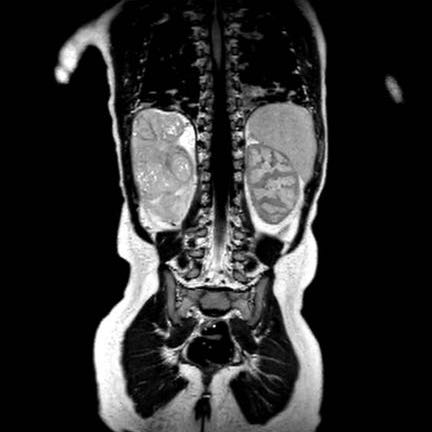

Hình ảnh chuỗi xung T2W mặt phẳng coronal cho thấy một khối u không đồng nhất ở thận trái với các thành phần nang nhỏ.

Khối u ngấm thuốc kém hơn so với phần nhu mô thận bình thường còn lại ở ngoại vi.

Các thành phần đặc của khối u cho thấy hạn chế khuếch tán rõ rệt (mũi tên).

Đây là u Wilms ở bé trai năm tuổi. Hóa trị tiền phẫu được thực hiện theo phác đồ Umbrella của SIOP-RTSG, sau đó tiến hành cắt thận.